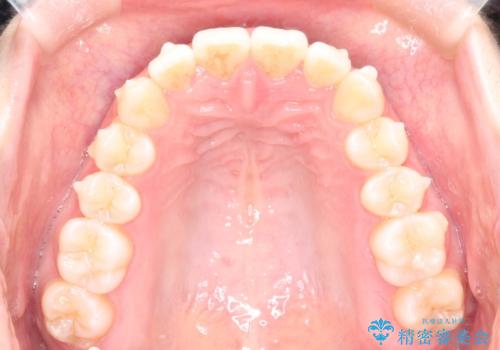

前歯のがたつきをインビザラインで目立たない矯正

- 上下の前歯のがたつきを主訴に来院されました。

マウスピースでの矯正を希望されたので、インビザラインで矯正治療を行うこととしました。

インビザラインではシュミレーションによりどのように歯が動くかを確認して矯正することができるので、患者様も安心して矯正をすることができました。